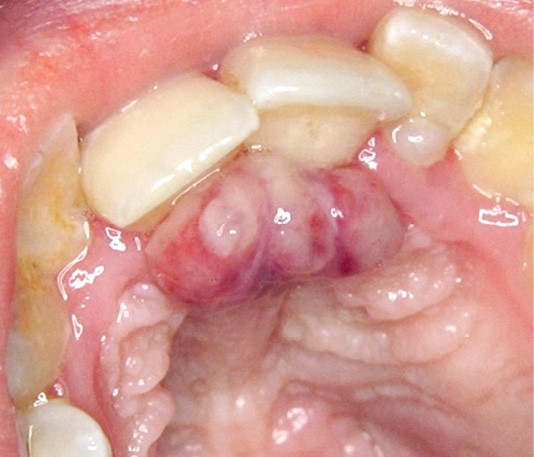

1. Épulis inflammatoire (plasmocytaire)

- Nodule indolore, pédiculé, érythémateux, parfois ulcéré (fig. 1a).